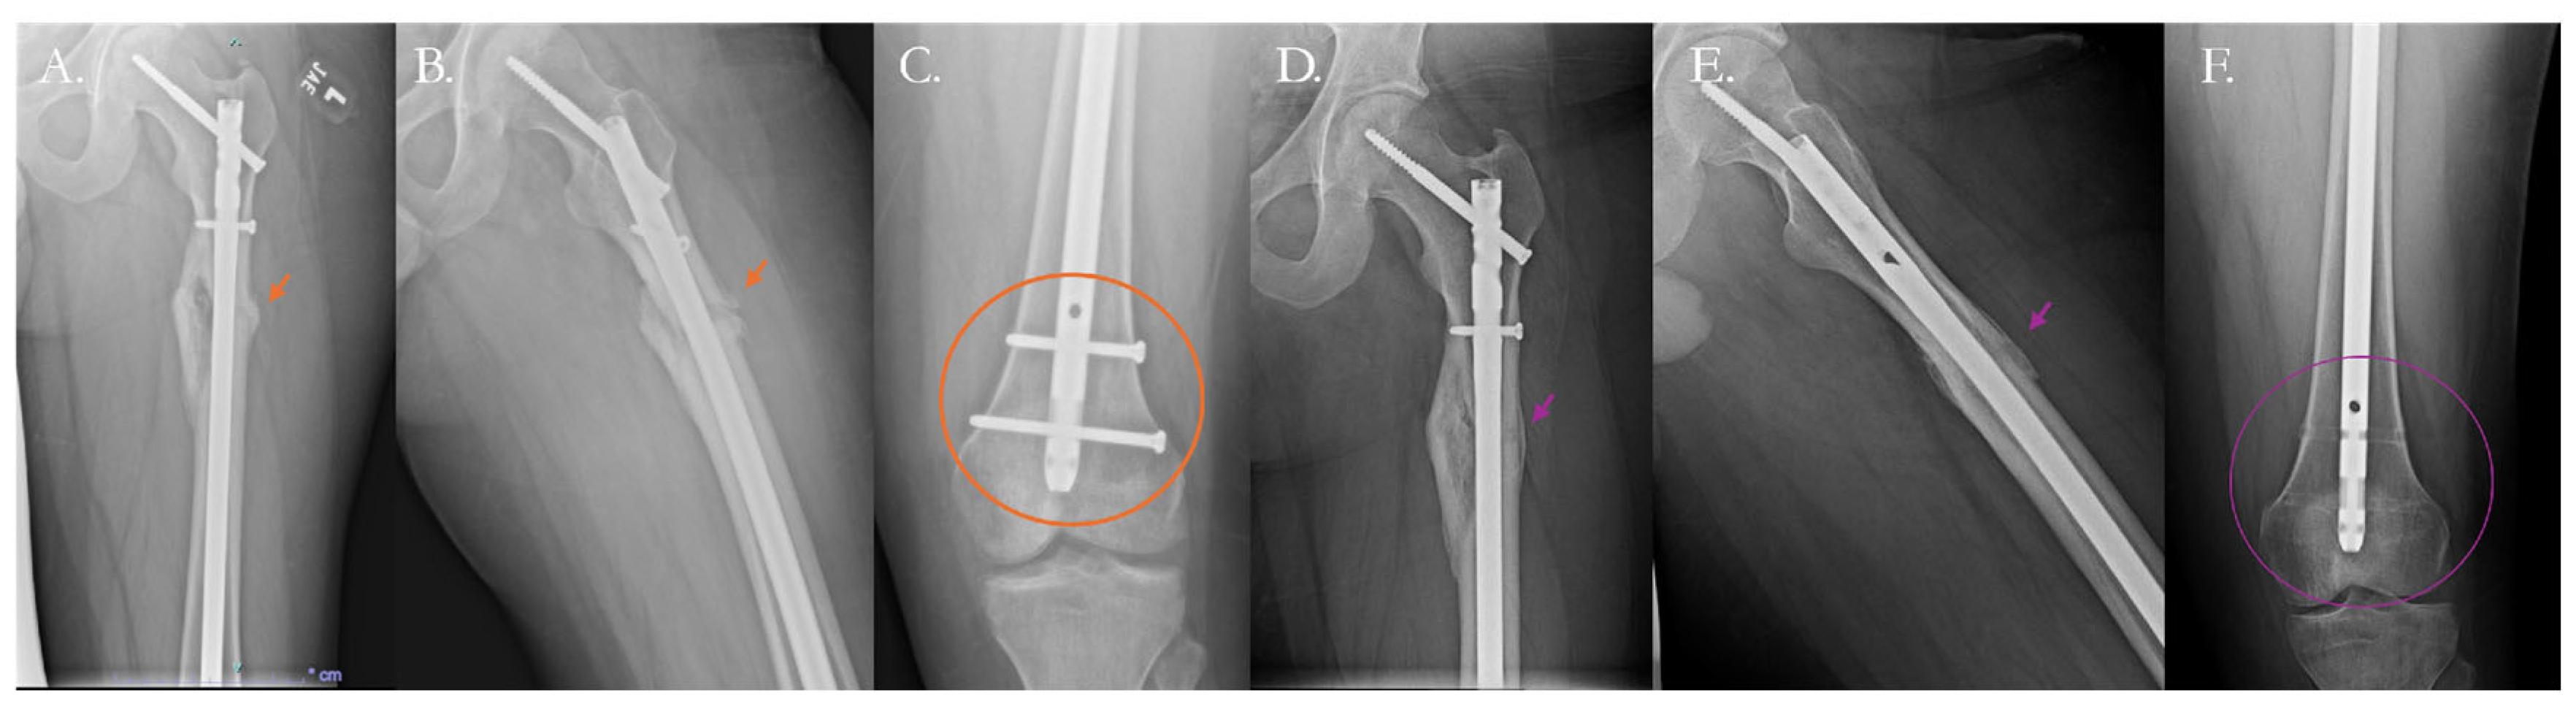

- Mittal, K.K.; Gupta, H.; Kaushik, N. Reunion of Post Nail Aseptic Non-Union of Diaphyseal Femoral Fractures by Augmentation Plating, Decortication and Bone Grafting–Replacement for Exchange Nailing. Injury 2021, 52, 1529–1533. [Google Scholar] [CrossRef]

- Rouse, B.J.; Sheridan, G.A.; Page, B.J.; Fragomen, A.T.; Rozbruch, S.R. Hypertrophic Nonunion Management with Distraction Osteogenesis: A Scoping Review of the Literature. OTA Int. 2024, 7, e342. [Google Scholar] [CrossRef]

- Fragomen, A.T.; Wellman, D.; Rozbruch, S.R. The PRECICE Magnetic IM Compression Nail for Long Bone Nonunions: A Preliminary Report. Arch. Orthop. Trauma. Surg. 2019, 139, 1551–1560. [Google Scholar] [CrossRef] [PubMed]